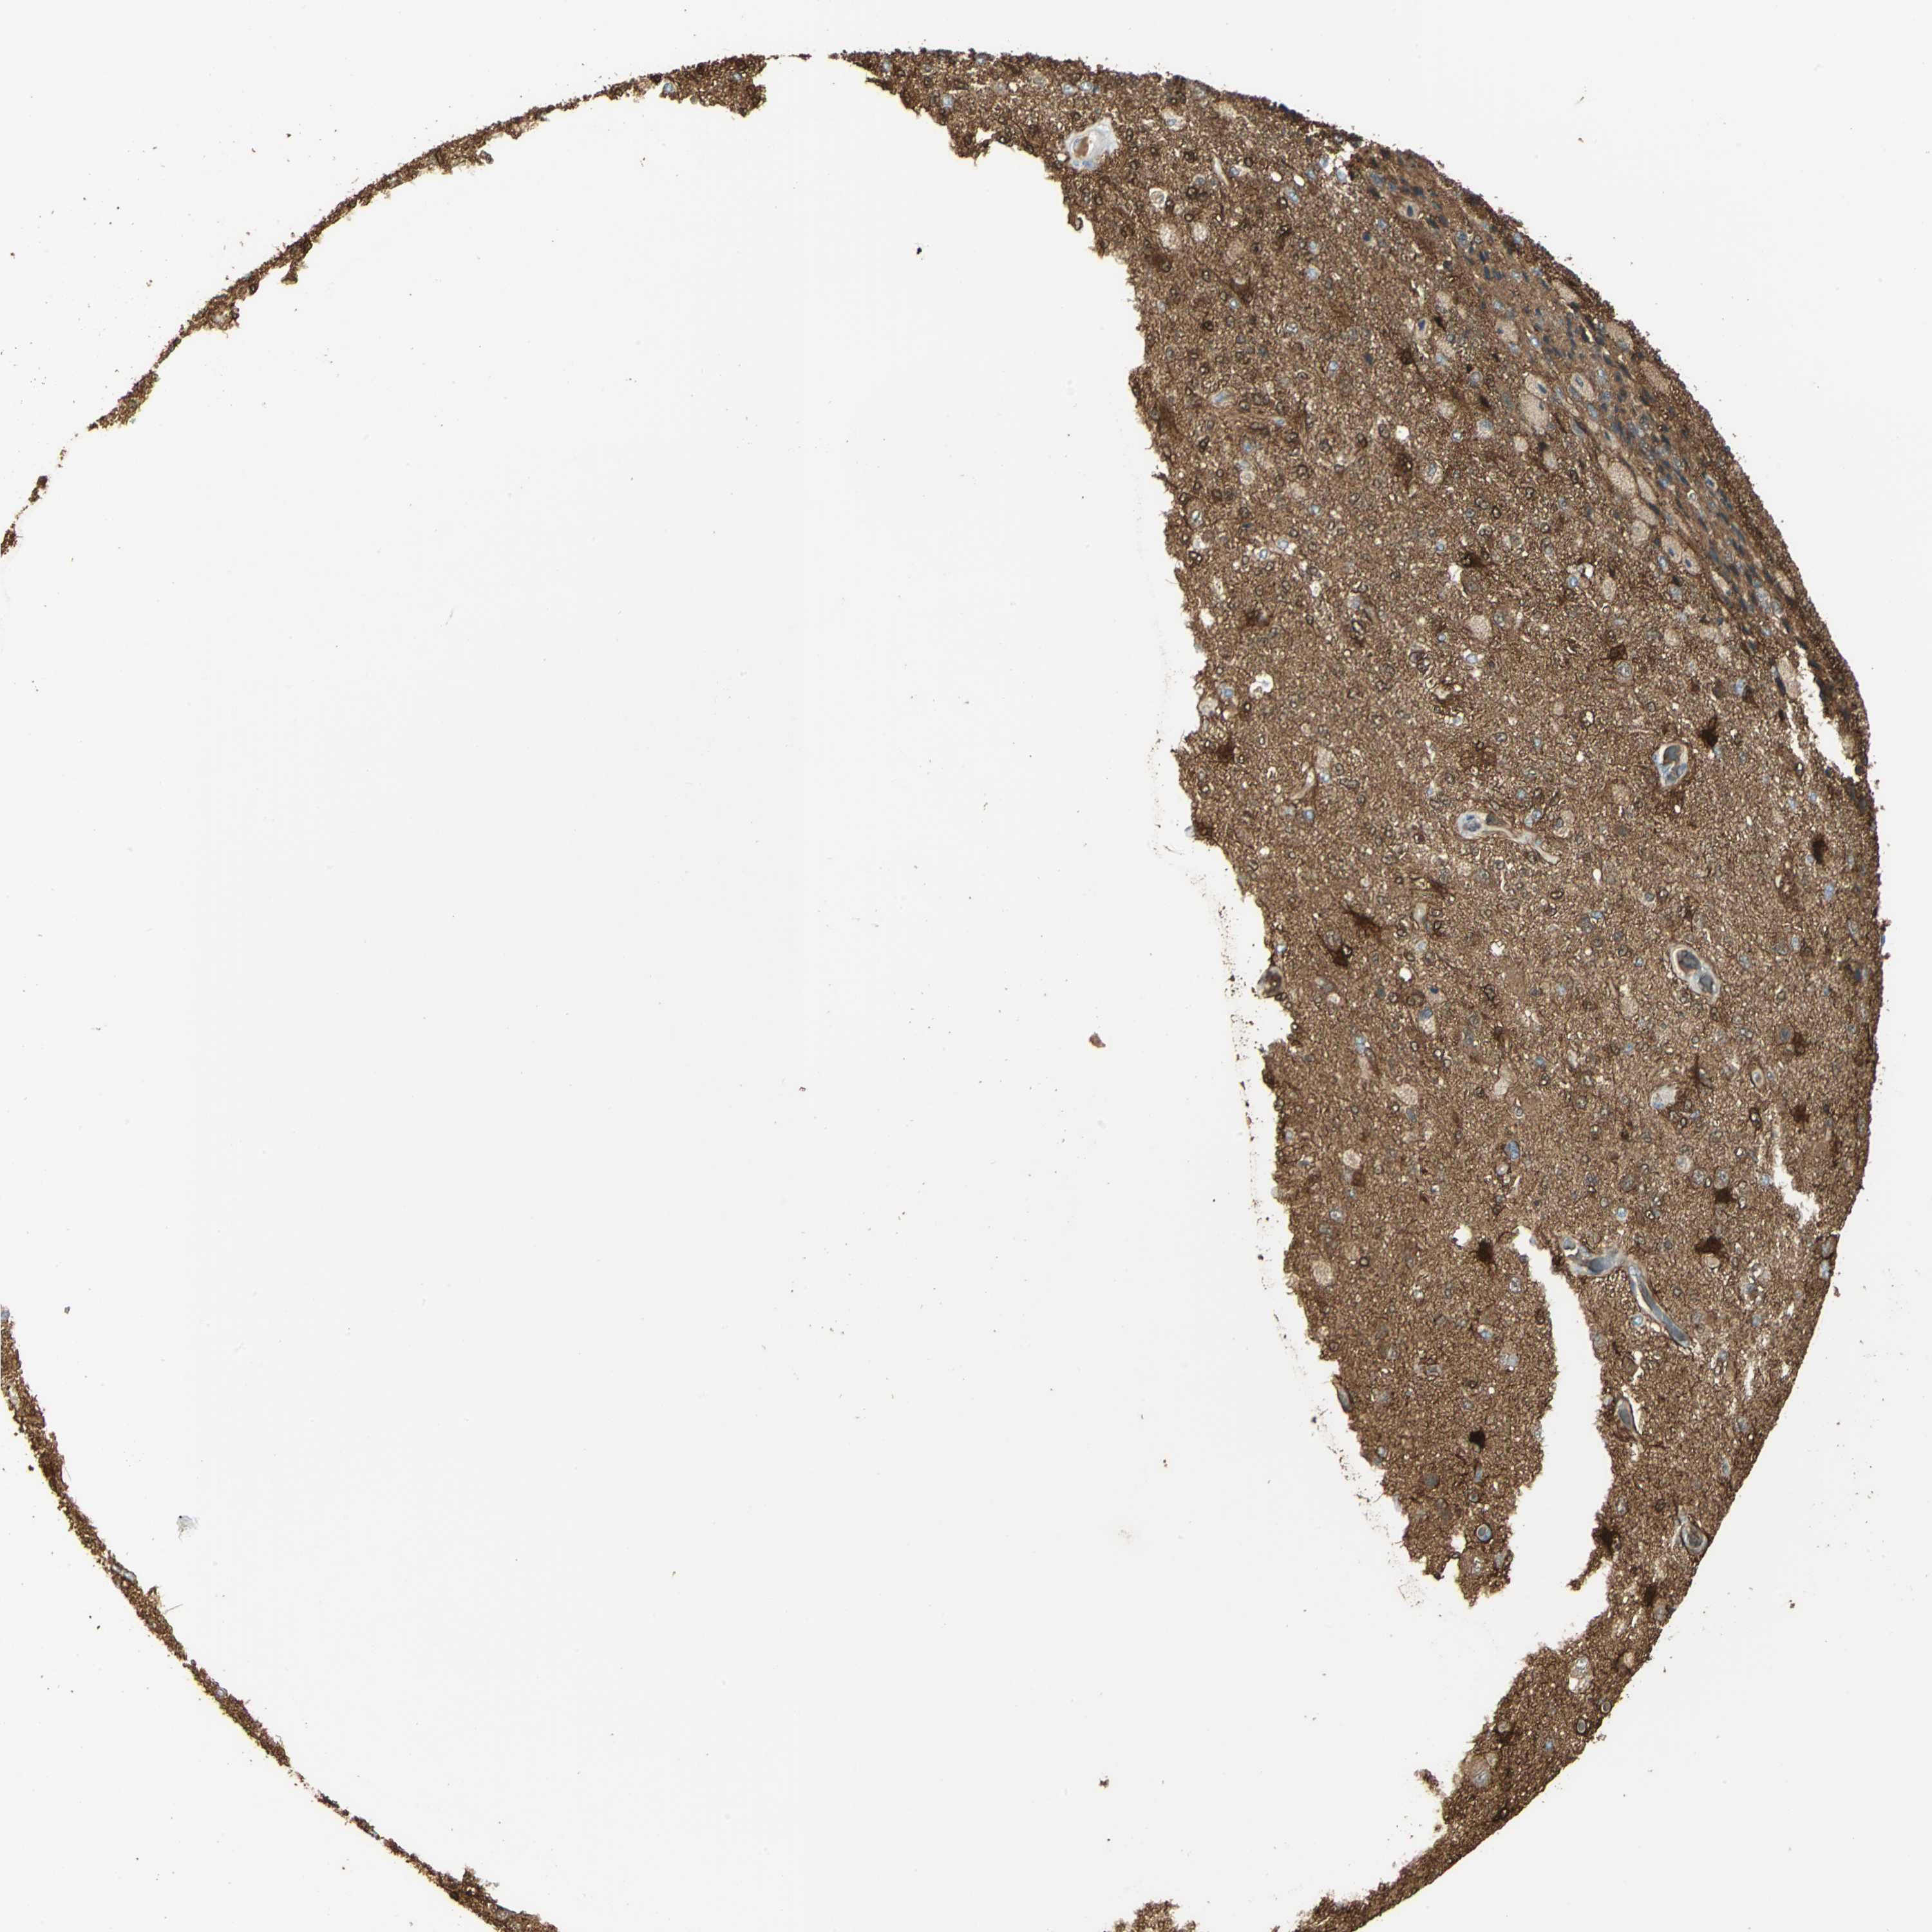

GLIOMA - Protein expressioni

A mouse-over function shows sample information and annotation data. Click on an image to view it in a full screen mode. Samples can be filtered based on level of antibody staining by selecting one or several of the following categories: high, medium, low and not detected. The assay and annotation is described here.

Note that samples used for immunohistochemistry by the Human Protein Atlas do not correspond to samples in the TCGA dataset.

Antibody stainingi

Antibody staining in the annotated cell types in the current human tissue is reported as not detected, low, medium, or high, based on conventional immunohistochemistry profiling in selected tissues. This score is based on the combination of the staining intensity and fraction of stained cells.

Each image is clickable and will lead to virtual microscopy that enables deeper exploration of all samples and also displays staining intensity scores, fraction scores and subcellular localization as well as patient and tissue information for each sample.

Antibody HPA006308

Antibody HPA071064

Glioma, malignant, Low grade

Glioma, malignant, High grade